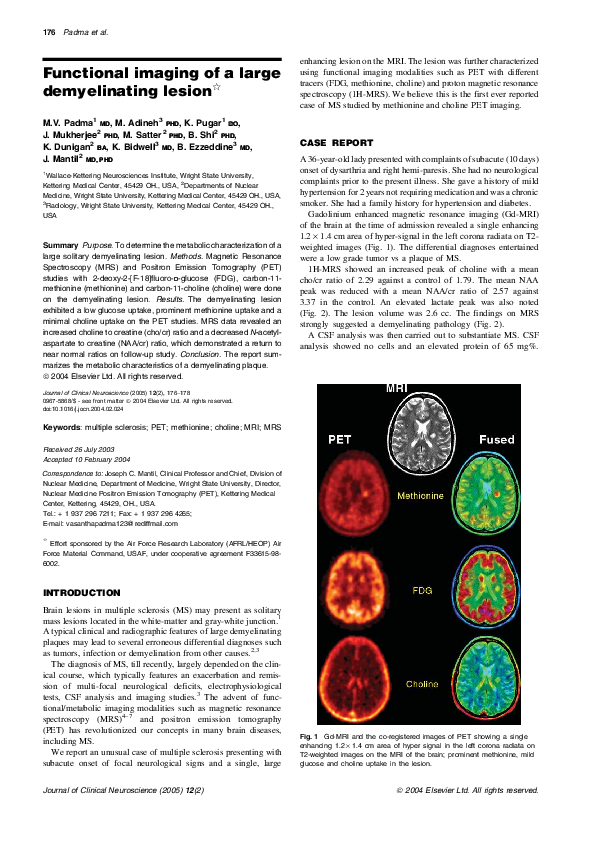

Pdf Functional Imaging Of A Large Demyelinating Lesion Jogeshwar Mukherjee Academia Edu